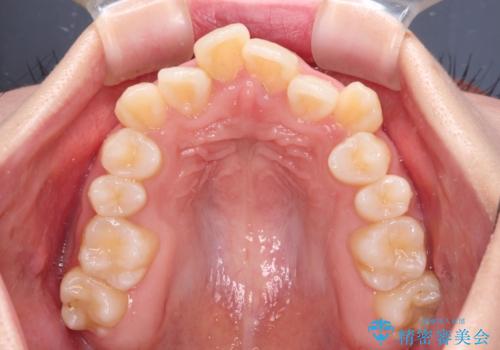

- 上下前歯の八重歯やデコボコと、唇の閉じにくさを気にして来院された患者様です。

口元の突出感を改善するため、上下左右の第一小臼歯4本を抜歯し、ワイヤー装置にて矯正治療を行うこととしました。

デコボコの解消で歯が磨きやすくなり、抜歯矯正により口元の突出感が大幅に改善され、スッキリした口元になりました。